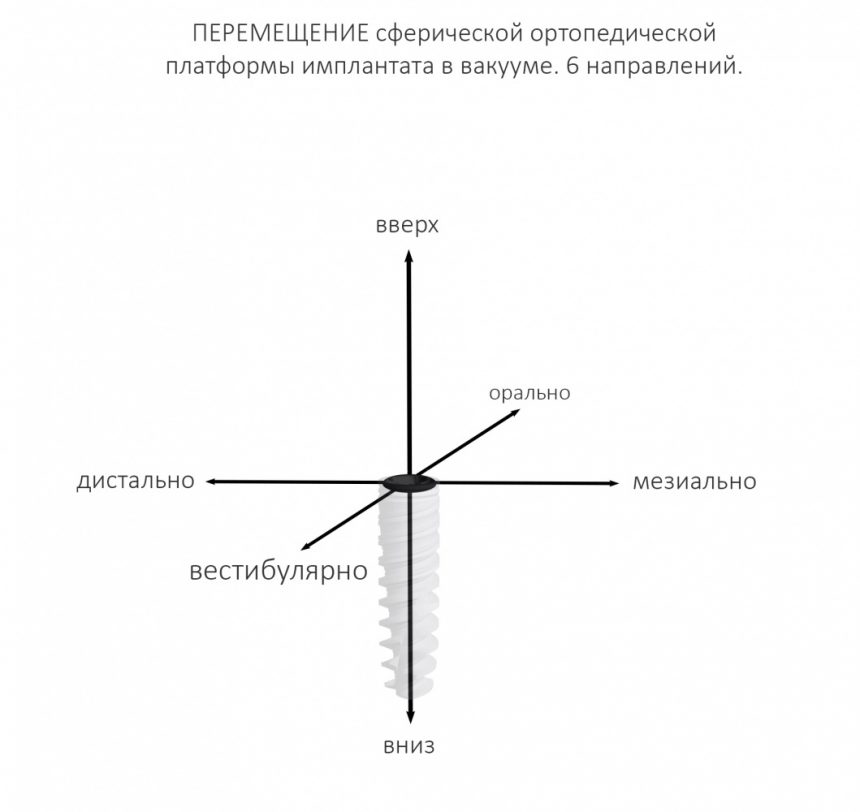

Для ортопеда наиболее важной частью имплантата является ортопедическая платформа (конус или шестигранник, кстати?:-)), и если мы, для простоты понимания, возьмём её за точку, то эта точка может перемещаться в альвеолярном гребне в шести направлениях:

Либо, если еще больше упростить, эта точка может перемещаться в двух направлениях окклюзионной плоскости (наружу-внутрь, вперед-назад), плюс направление вверх-вниз (т. е. погружение):